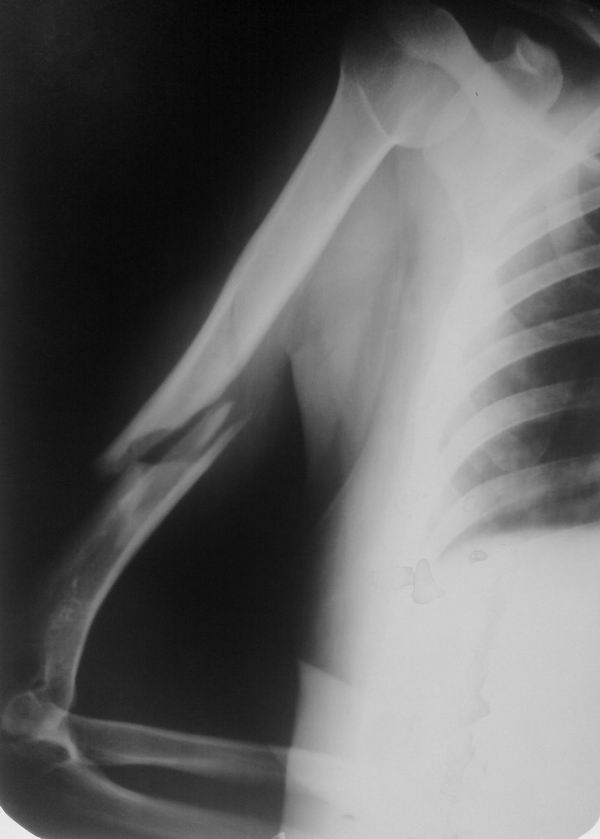

[Ortho] Ложный сустав плечевой кости

Исходный снимок